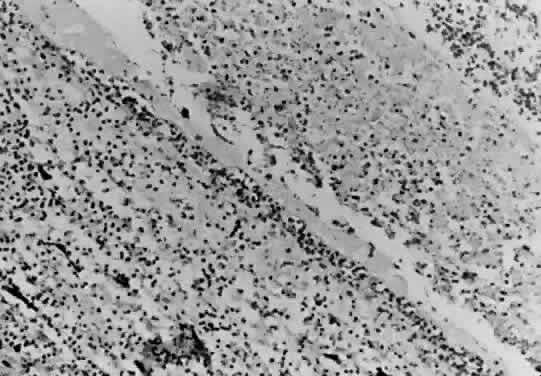

An animal model of ocular toxoplasmosis was produced in a nonhuman primate, the cynomolgus monkey, by Culbertson and coworkers.37 The retinochoroiditis was induced by direct inoculation of Toxoplasma organisms into the retina through the pars plana under direct microscopic visualization. The focal necrotizing retinitis lesions had morphologic and histopathologic resemblance to the lesion seen in humans, and the course of retinochoroiditis closely resembled the course of the disease in humans. The cynomolgus monkey was found to be resistant to the RH strain of T. gondii and developed no evidence of systemic disease and no encephalitis. Healing of the retinochoroiditis was associated with scar formation with atrophic scar and variable pigmentation. Histologic studies reveal mononuclear inflammatory reaction with evidence of areas of necrosis seen in the retina (Fig. 4). The monkey appears to be a good animal model for the study of ocular toxoplasmosis. Pavesio and associates report an animal model of acquired retinochoroiditis in hamsters.38

Fig. 4. Section of the retina of a cynomolgus monkey infected with T. gondii shows extensive retinal necrosis with disruption of the normal retinal architecture, mononuclear cell infiltration, and severe choroiditis. (H & E, × 100)